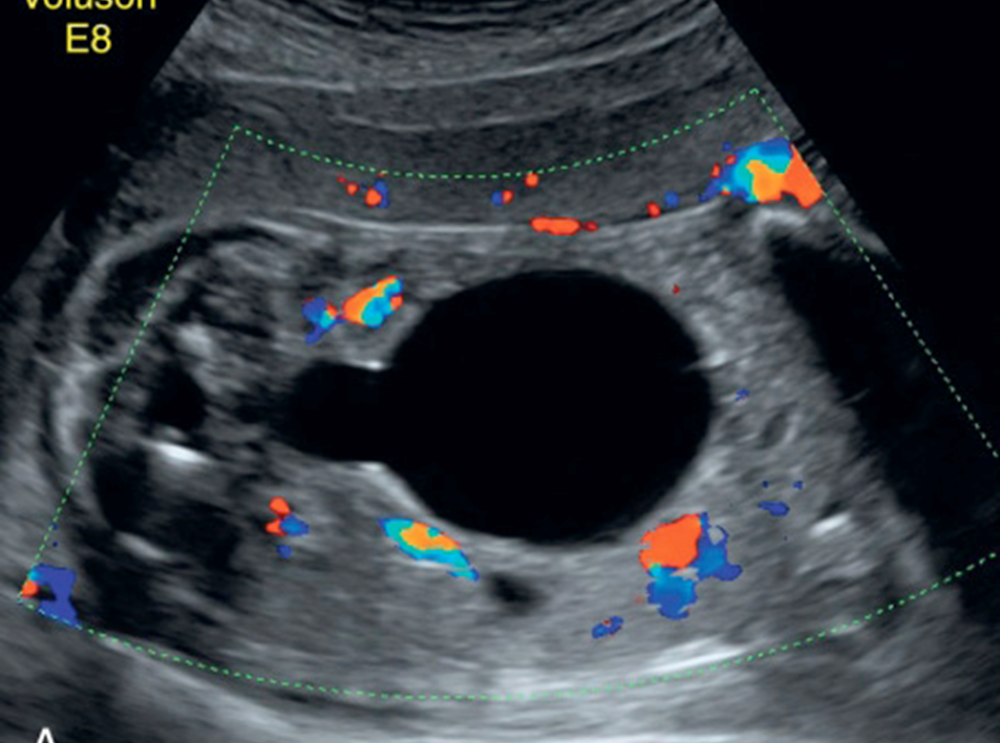

Ovarian Cyst